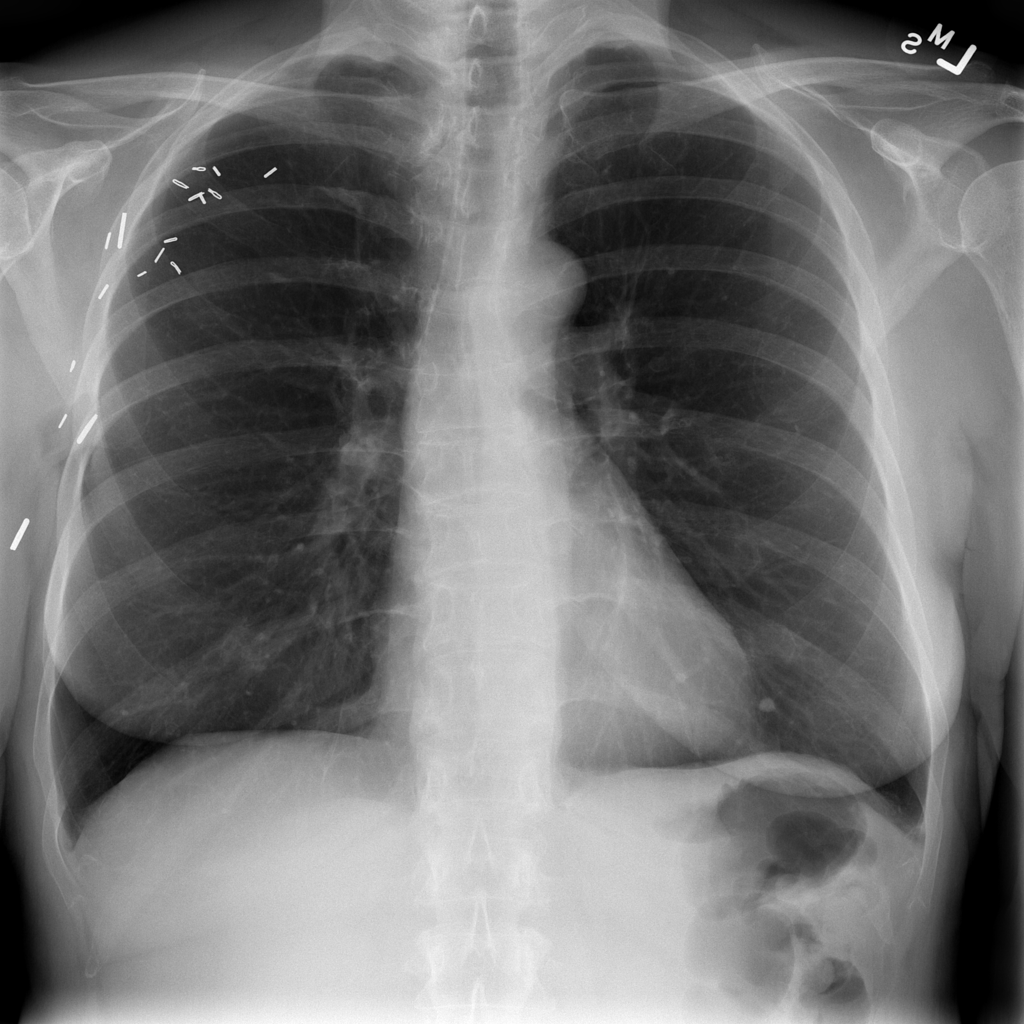

PAT-F3E7 · IMG-002Nodule

PAT-F3E7 · IMG-002

PA